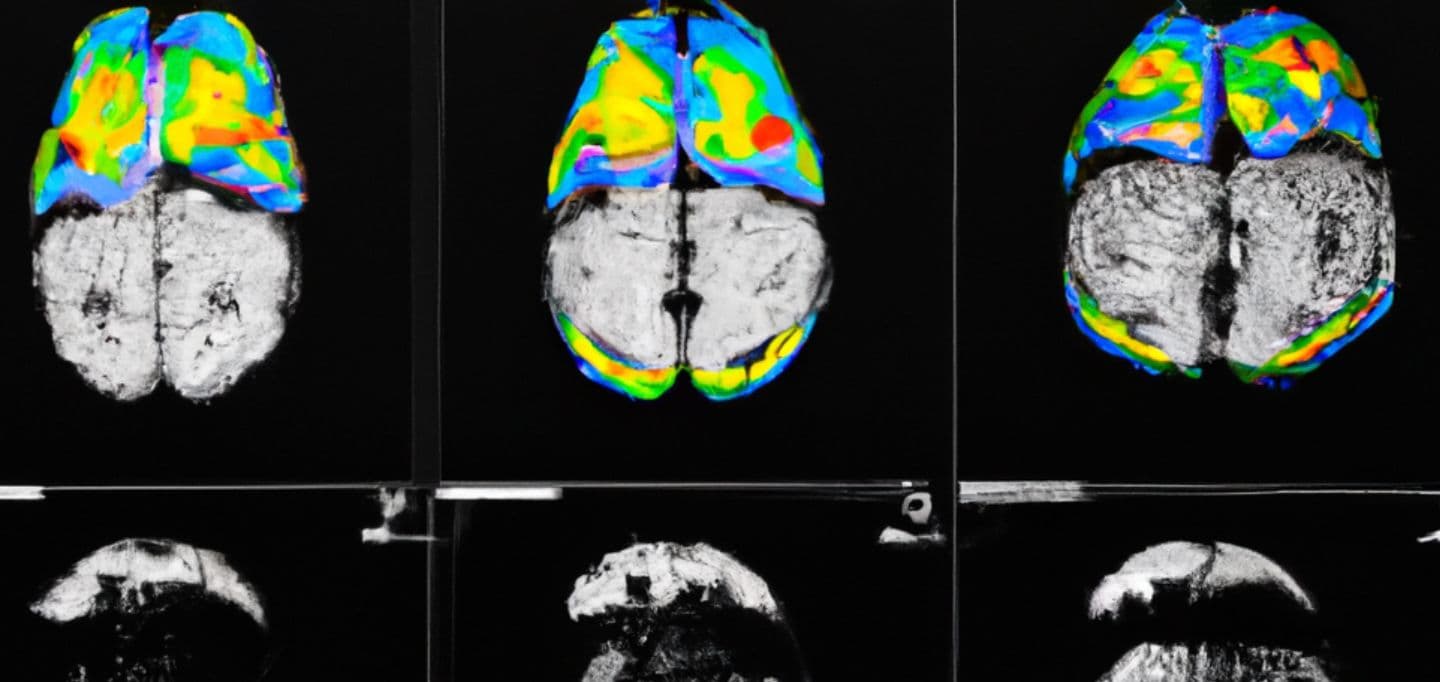

De todos os estudos, ao menos 40 focam em neurologia e avaliam diretamente o funcionamento e a estrutura do cérebro de um usuário de pornografia na internet. Outros mostram que crianças com uma média de 12 anos de idade que acessam o celular já estão sendo expostas a esse tipo de conteúdo.